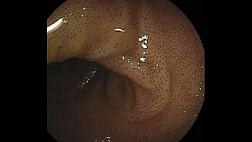

Иллюстрация №2: Выраженная кишечная метаплазия слизистой культи желудка.

При гастроскопии в просвете культи пищевода определяется инородное тело ,неправильной продолговатой формы , состоящее из мышечных волокон ,частично разволокненных. Инородное тело полностью обтурирует просвет в области эзофагогастроанастомоза, удалено с помощью петли. Далее при осмотре имеются продольные эрозии слизистой пищевода выше анастомоза, а также рубцовое сужение анастомоза до 0,7 см. Проведено эндоскопическое бужирование пищевода по струне-проводнику бужом 30 Fr(10 мм) . В культе желудка незначительное слизистое содержимое, а также выраженная кишечная метаплазия слизистой в дистальном отделе.